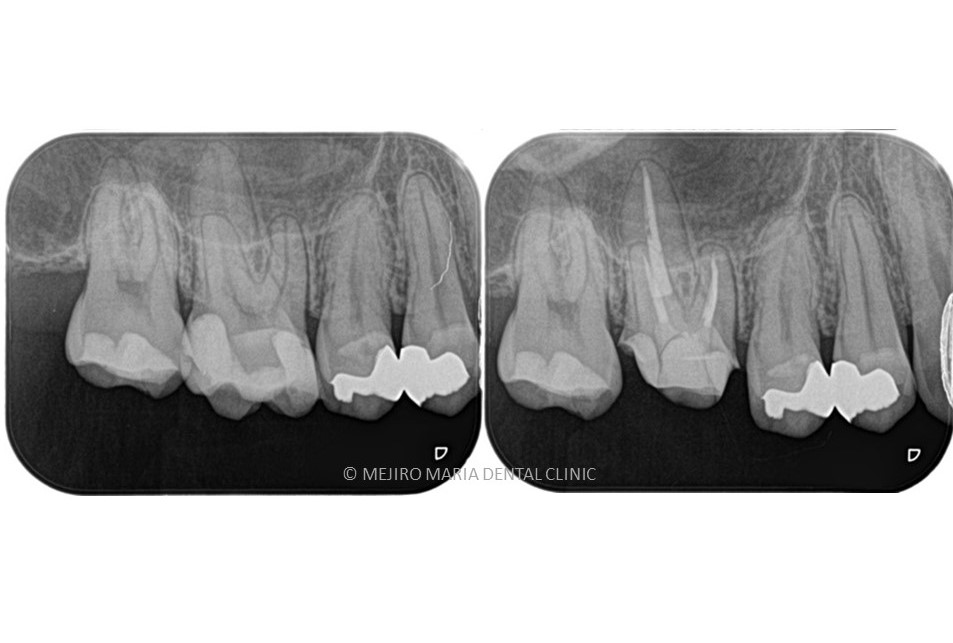

【症例】無症状で進行する虫歯・原因不明の歯肉の腫れを、コンセプトを守った初回根管治療(精密根管治療)で治癒

治療内容 抜髄(初回根管治療)|精密根管治療

治療期間 1週間

治療回数 2回

治療費用 181,500円(税込)

※支台築造処置を含む

リスク・副作用

• 治療計画は口腔内、歯牙の状況により変更する場合があります。

• 下顎に対するインプラントを含む外科的処置にて下歯槽神経を損傷した場合、顔面に知覚麻痺が生じる場合があります。

• 当院の補綴処置の保証期間は5年間ですが、3ヶ月〜6ヶ月の定期的なメインテナンス、定期検診に来院されていない場合は適用されません。